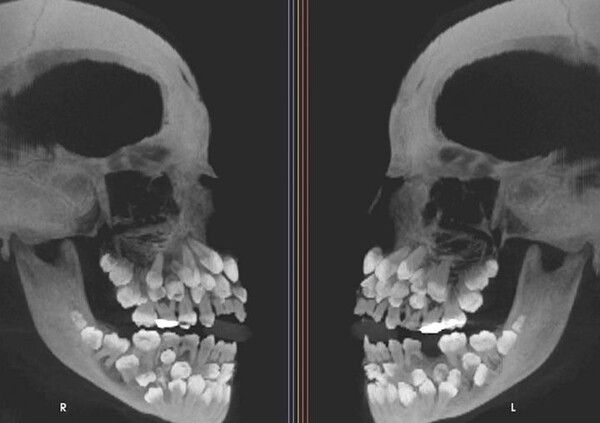

사진 = 뉴시스

브라질에서 11세 소녀의 입 안에서 81개의 치아가 발견되는 전례 없는 희귀 사례가 보고됐다.

A양은 유치 18개, 영구치 32개, 과잉치 31개, 총 81개의 치아를 가지고 있었다.

의료진은 CT 검사를 통해 다발성 과치증과 흔히 동반되는 구개열, 쇄골두개 이형성증, 가드너 증후군 같은 질환은 나타나지 않았다고 전했다.

브라질 미나스제라이스주 후이즈데포라 연방대학 의사들은 "다발성 과치증의 경우 대부분 치아가 1~2개 더 많지만, A양처럼 유전적 증후군이 없는데 과잉 치아가 31개 발견된 것은 전례가 없다"고 말했다.

이 소녀는 수 많은 과잉치로 인해 치료에도 어려움을 겪고 있다. 과잉치 발치 시에는 턱 뼈 손상을 야기할 수 있기에 신중히 접근해야 하고, 잇몸 밖으로 드러나지 않은 치아도 있어 진짜 치아와 과잉치를 구분하는 일도 쉽지 않다.